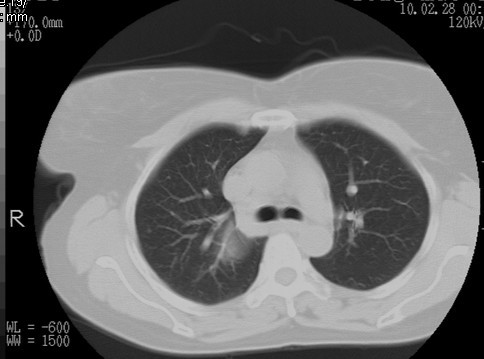

以下是引用随光逐影在2010-3-1 8:36:00的发言:[br]右上纵隔囊性占位性病变,考虑支气管囊肿,不排除神经源性肿瘤。